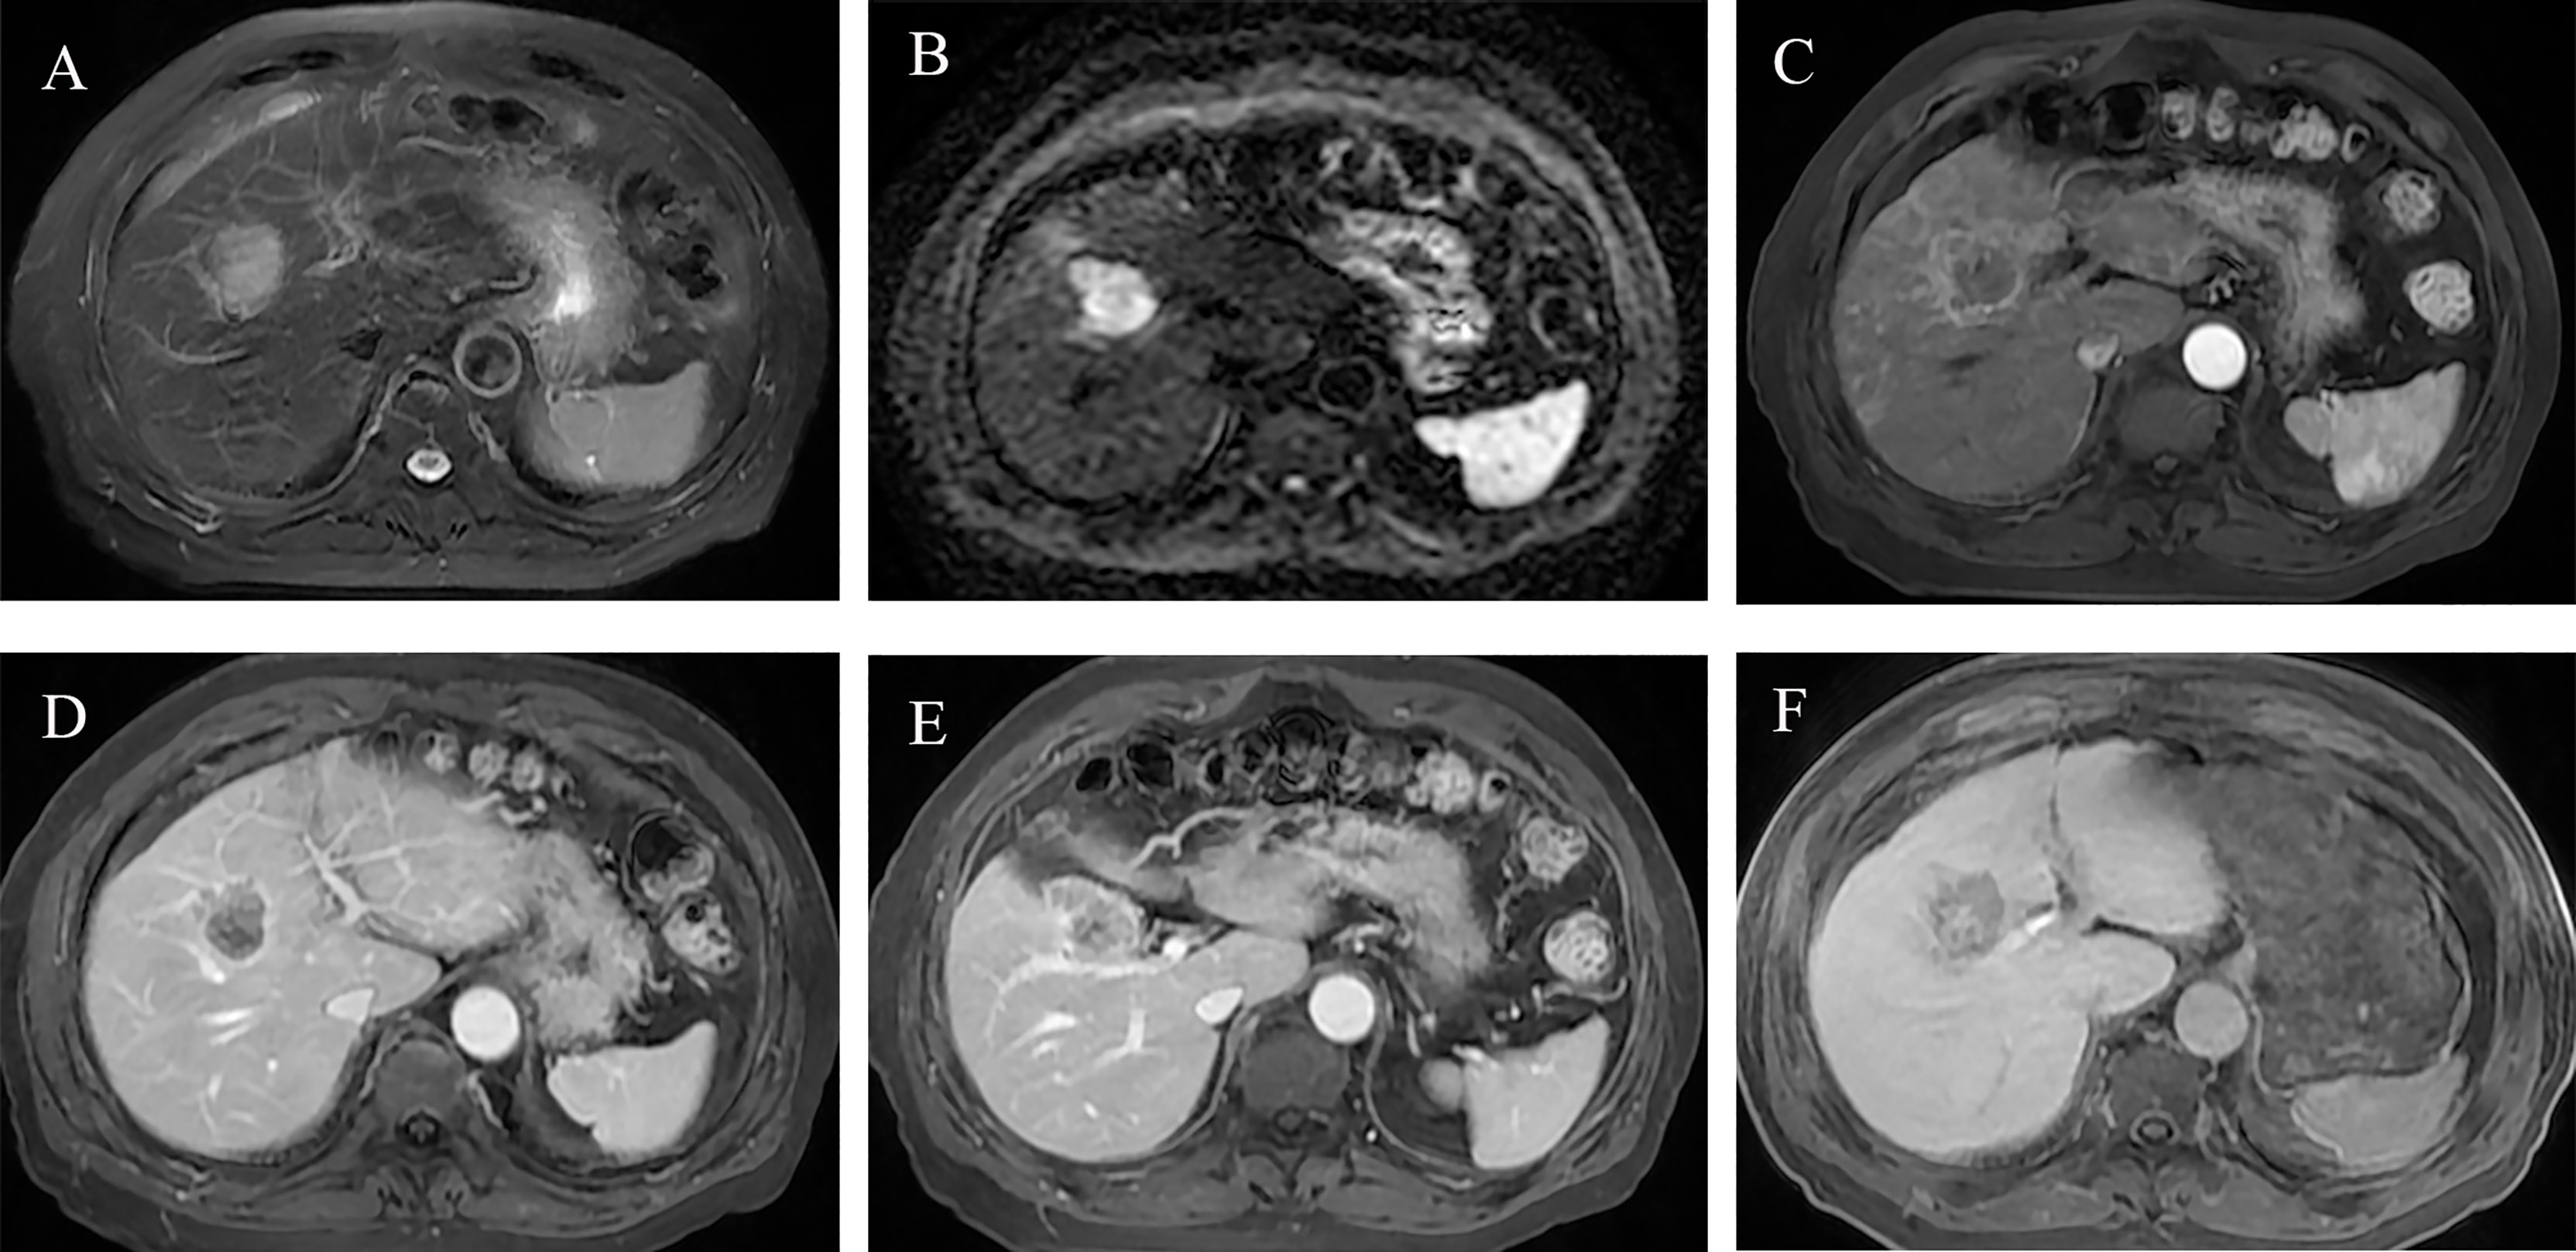

The risk score of each patient was calculated by the HBP-pre model, ranging from −1.98 to 3.03. Patients were divided into two groups (low-risk group and high-risk group), taking 75% of the risk score distribution range as the dividing point (the cutoff score was 0.84806, the corresponding nomogram 24-month RFS probability is 0.47845). There were 116 patients in the low-risk group, of whom 23 patients had early recurrence, and the recurrence rate was 19.83%. There were 39 patients in the high-risk group, of whom 29 patients had early recurrence; the recurrence rate was 74.36%, and the median recurrence time was 12 months. RFS rate was observed in each risk group (p < 0.001, by the log-rank test) (Figure 5B). The ability of risk identification was proved by this model This model successfully predicted that a patient was at high-risk group, and its MRI was shown in Figure 6.

Figure 6 Preoperative MR images of early recurrence after anatomical hepatectomy in patients with hepatocellular carcinoma. A 72-year-old male with AFP-L3, PT, and GGT levels (negative, 10.7 s, 38 U/L) was hospitalized due to abdominal discomfort. Before operation, Gd-BOPTA MRI found a 3.7-cm lesion in hepatic segment V, with typical HCC features: mild hyperintensity on T2-weighted imaging (A), hyperintensity on diffusion-weighted imaging (B), and hypointensity on HBP (F). Rim arterial phase hyperenhancement present (C) and incomplete radiological capsule enhancement (E) were risk factors of early recurrence in our study. Arterial peritumoral enhancement, an independent risk factor for early recurrence, was presented on arterial phase and portal phase (C, D), white arrow). Peritumoral hypointensity on HBP (F, white arrow), also an independent risk factor. After anatomical hepatectomy, postoperative follow-up presented that this patient suffered from intrahepatic distant recurrence at 3 months.